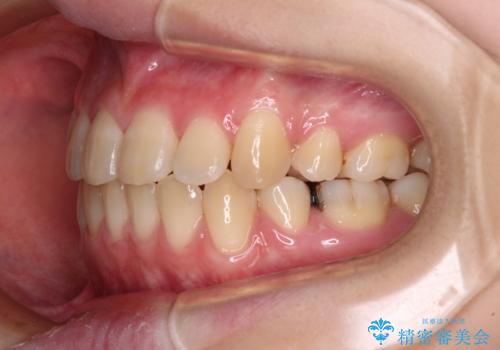

- 上下前歯が前方に飛び出しているとのことで来院された患者様です。

上下左右第一小臼歯4本を抜歯して、積極的に口元を引っ込めるよう、ワイヤー装置にて矯正治療を行うこととしました。

口元の突出感は著しく改善され、横顔の印象が大きく変化しました。